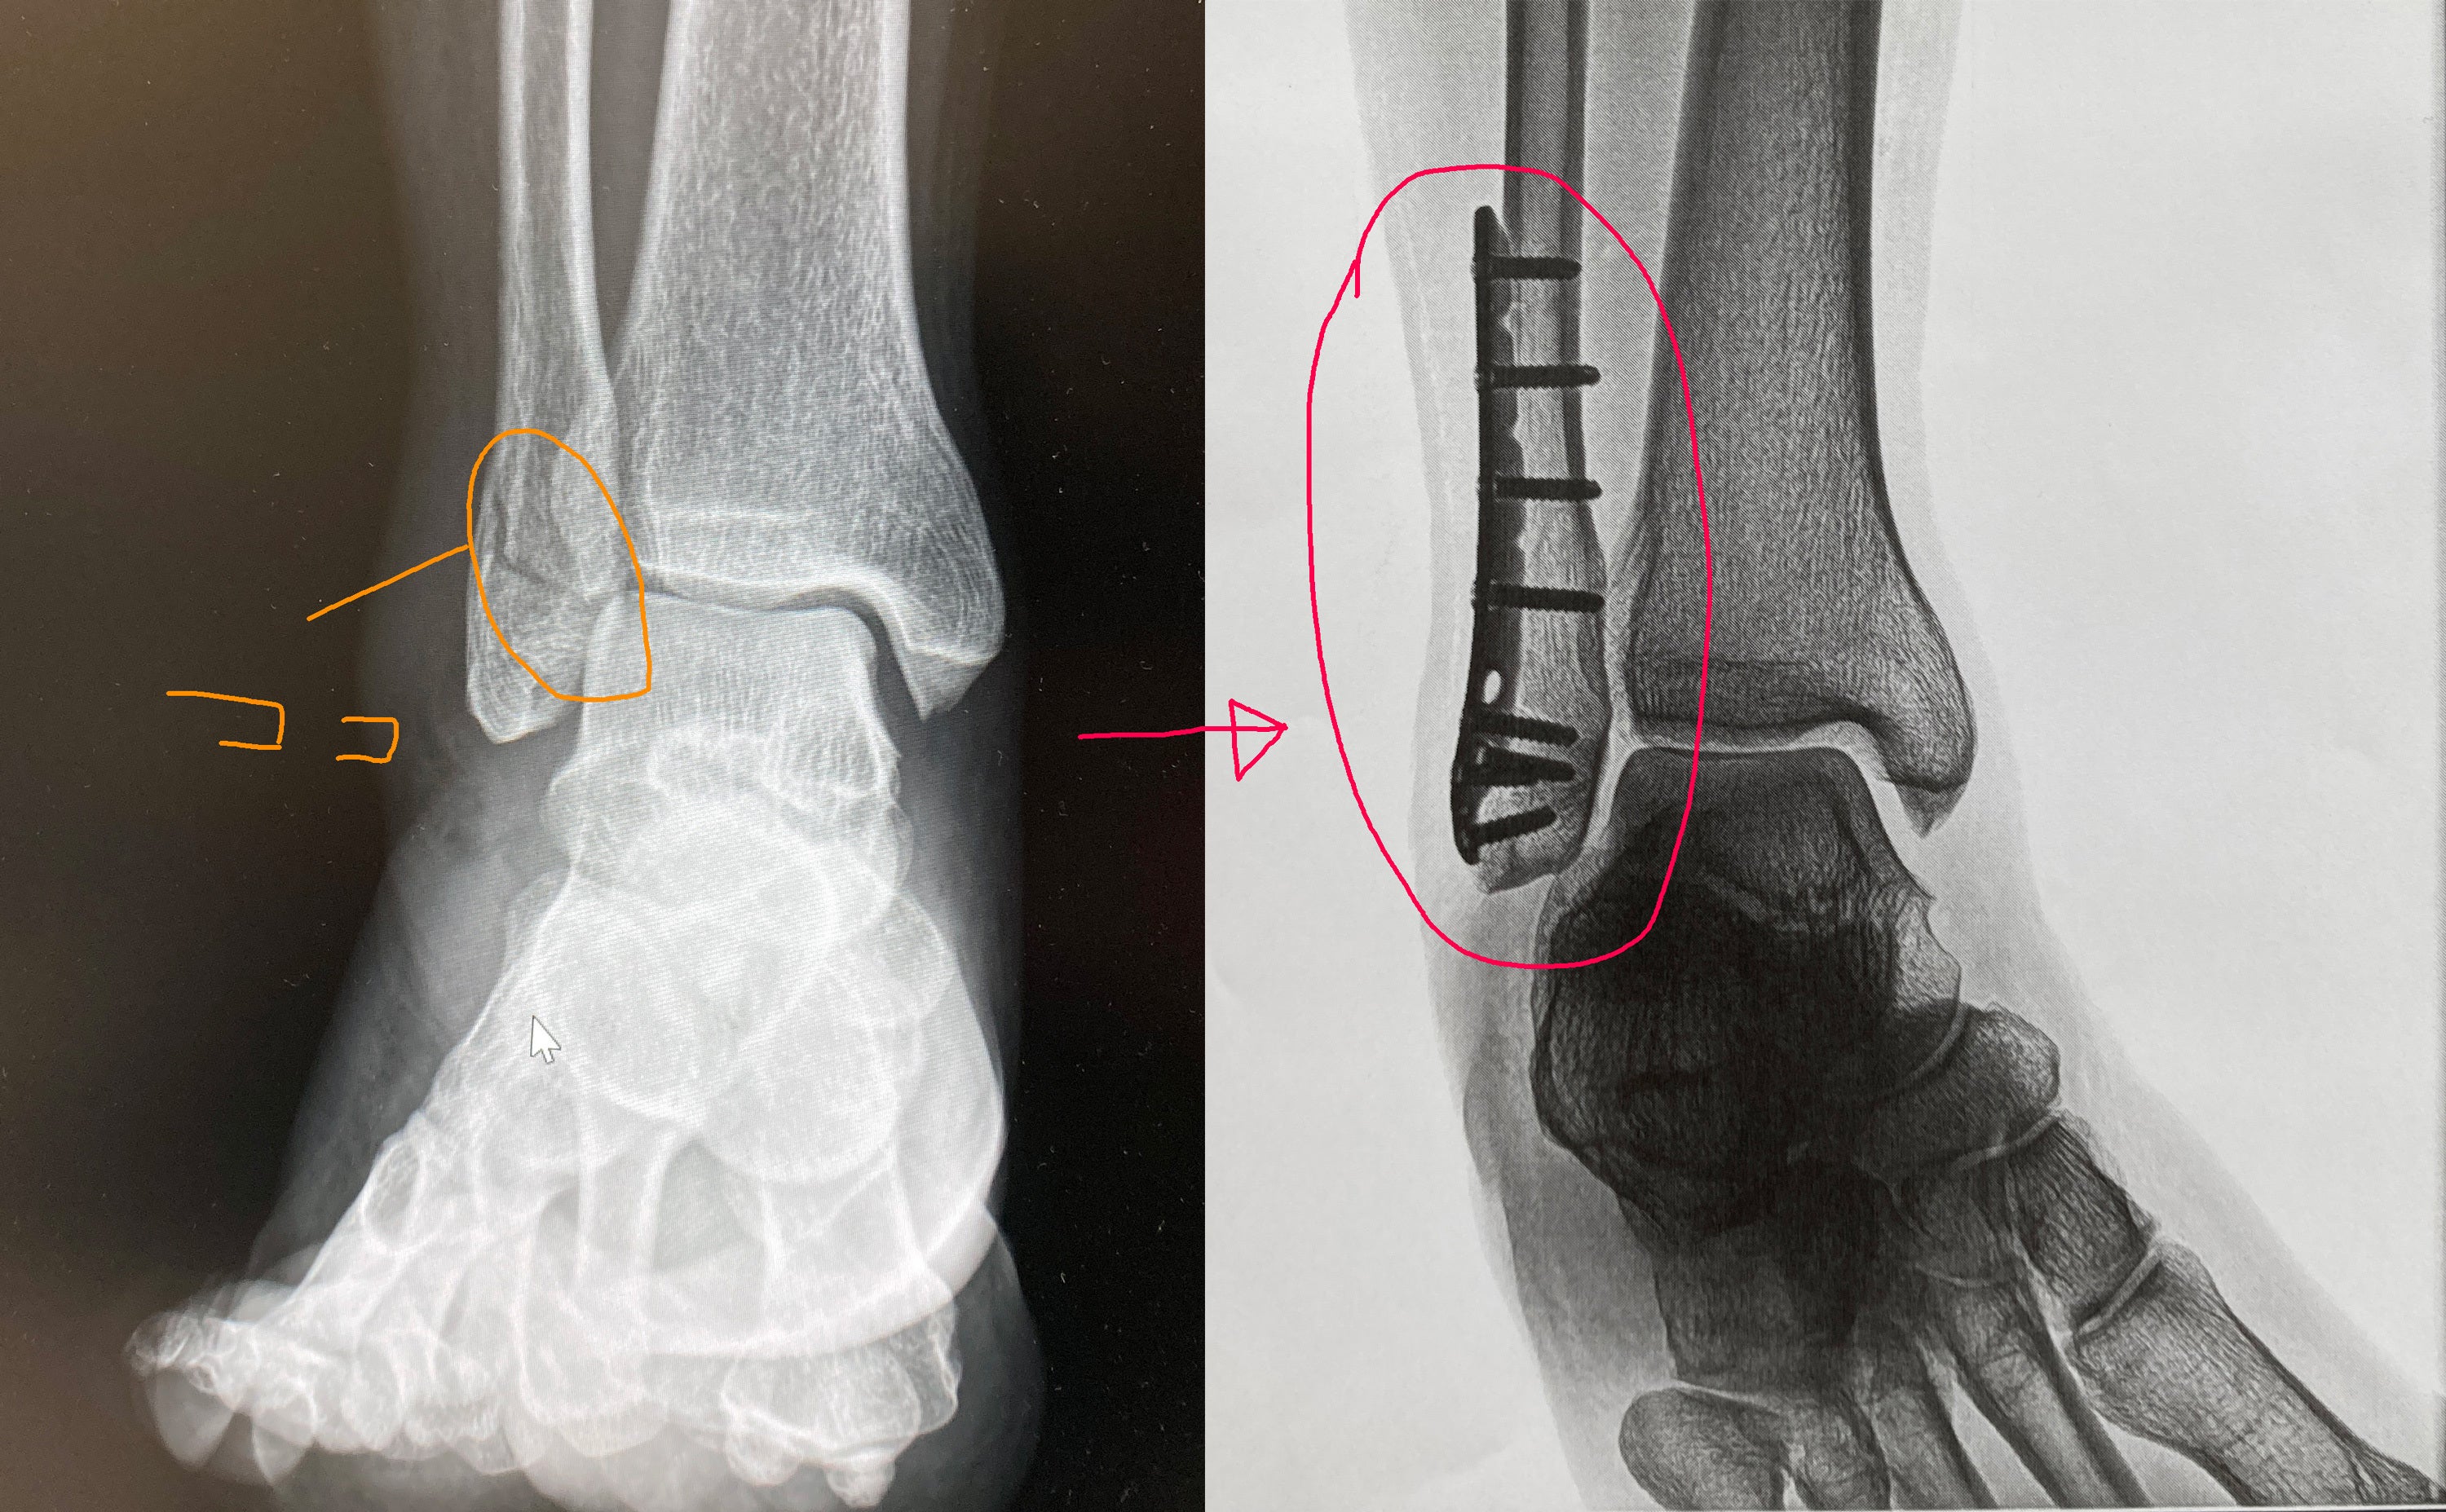

本プロジェクトをスタートして数日たった5月1日に右足首の腓骨をポキッと折ってしましました。

GW中ということもあり5月7日に手術。

今は自宅でリハビリ、来週から本格的にリハビリに入り、徐々にですが20日からレッスン再開していきます。